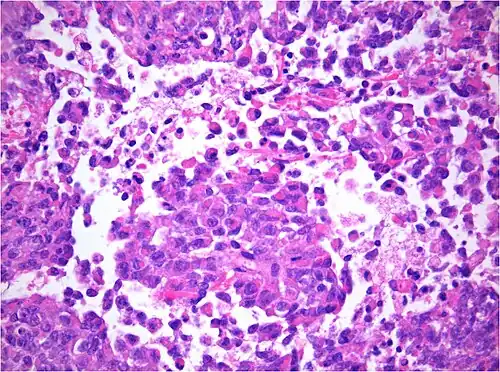

AT/RT and rhabdoid tumor share the term "rhabdoid" because under a microscope, both tumors resemble rhabdomyosarcoma.

Histology

The tumor histopathology is jumbled small and large cells. The tissue of this tumor contains many different types of cells including the rhabdoid cells, large spindled cells, epithelial and mesenchymal cells, and areas resembling primitive neuroectodermal tumor (PNET). As much as 70% of the tumor may be made up of PNET-like cells. Ultrastructure characteristic whorls of intermediate filaments are seen in the rhabdoid tumors (as with rhabdoid tumors in any area of the body). Ho and associates found sickle-shaped embracing cells, previously unreported, in all of 11 cases of AT/RT.[24]